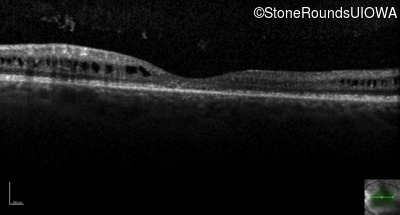

Optical Coherence Tomography - Right - 20/80

Exemplar / OCT Stack